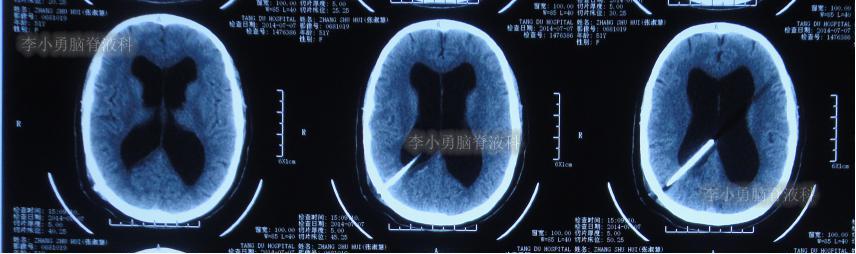

住院后3天即2016年8月19日,查头颅CT:幕上脑室扩张( 图-9 )。

图-9: 2016年8月19日头颅CT

第3次出院后21天即2016年9月23日,复查头颅CT:幕上脑室仍扩张( 图-10 )。

图-10: 2016年9月23日头颅CT